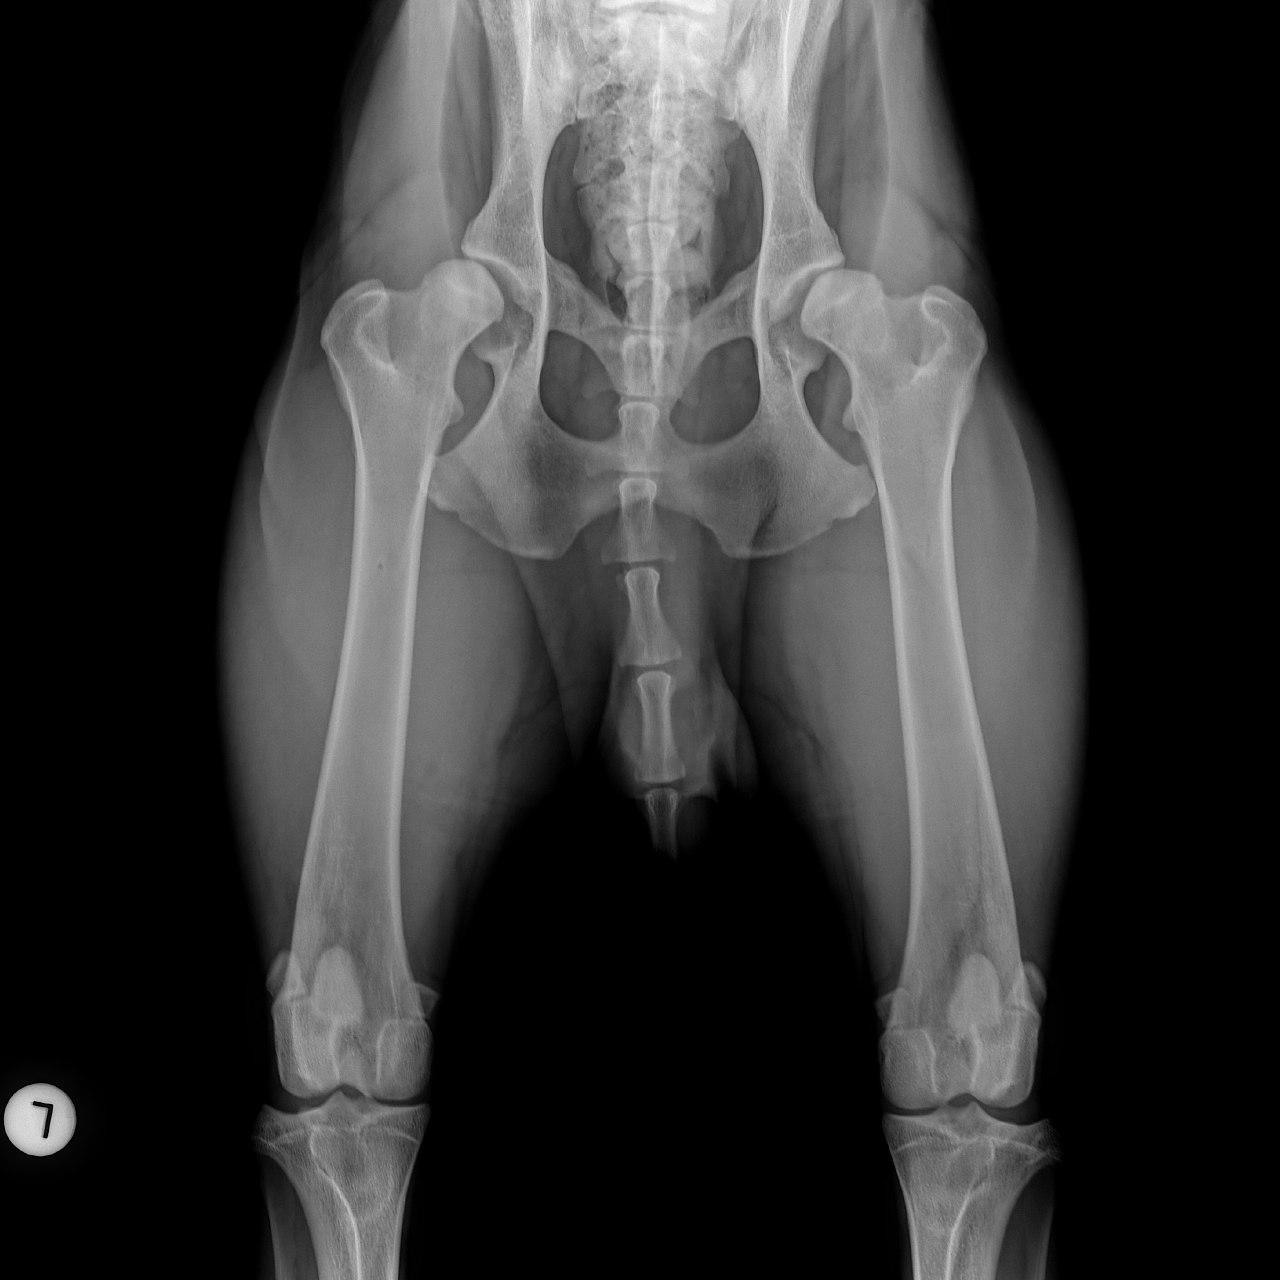

Mit der HD ist das so ne Sache..... die Vererbung spielt eine sehr große Rolle, ja. Aber bei unserer Peggy Zb ist es so, dass mehrere Generationen nachweislich HD und ED frei sind und auch frei von Spondylosen. Als einziger Hund überhaupt in der gesamten Zucht hat unsere Dame alles mitgenommen, was zu kriegen war;(: sie hat nicht nur schwere HD, weil ihre Hüfte viel zu locker ist, sondern dadurch bedingt am rechten Knie bereits schwere Arthrose und hinten links eine Sehenschwäche (durch Überlastung), weshalb sie dort durchtrittig ist. Und als würde das alles nicht schon vollkommen reichen, wurden aktuell auch noch mehrere heftige Spondylosen diagnostiziert;(. An einer Stelle ist sogar schon etwas abgebrochen8|.